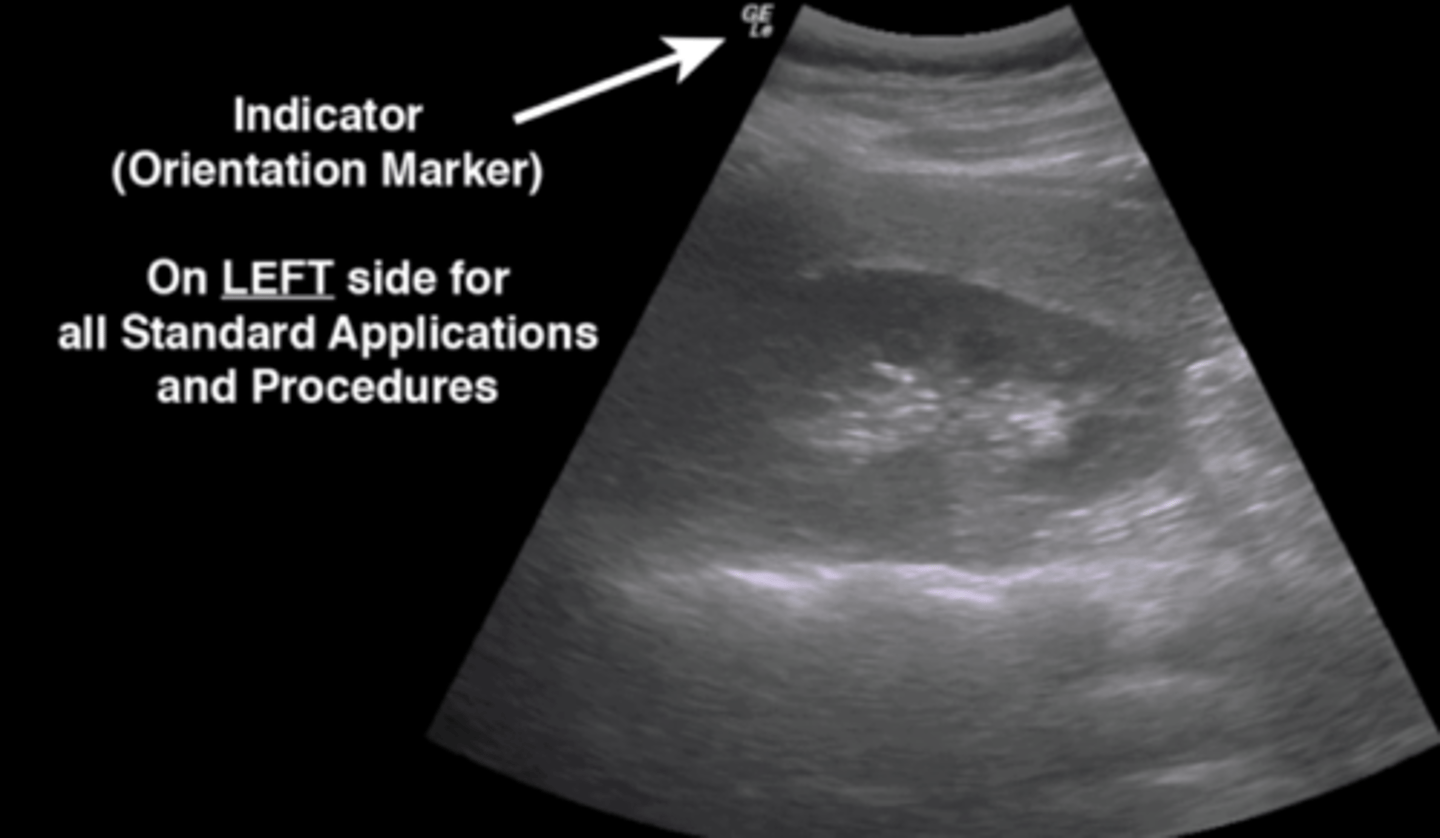

What is the purpose of the indicator on the probe?

Indicator = orientation marker; tells you right vs. left to orient you to the tissues

NOTE: on LEFT side for all standard applications and procedures